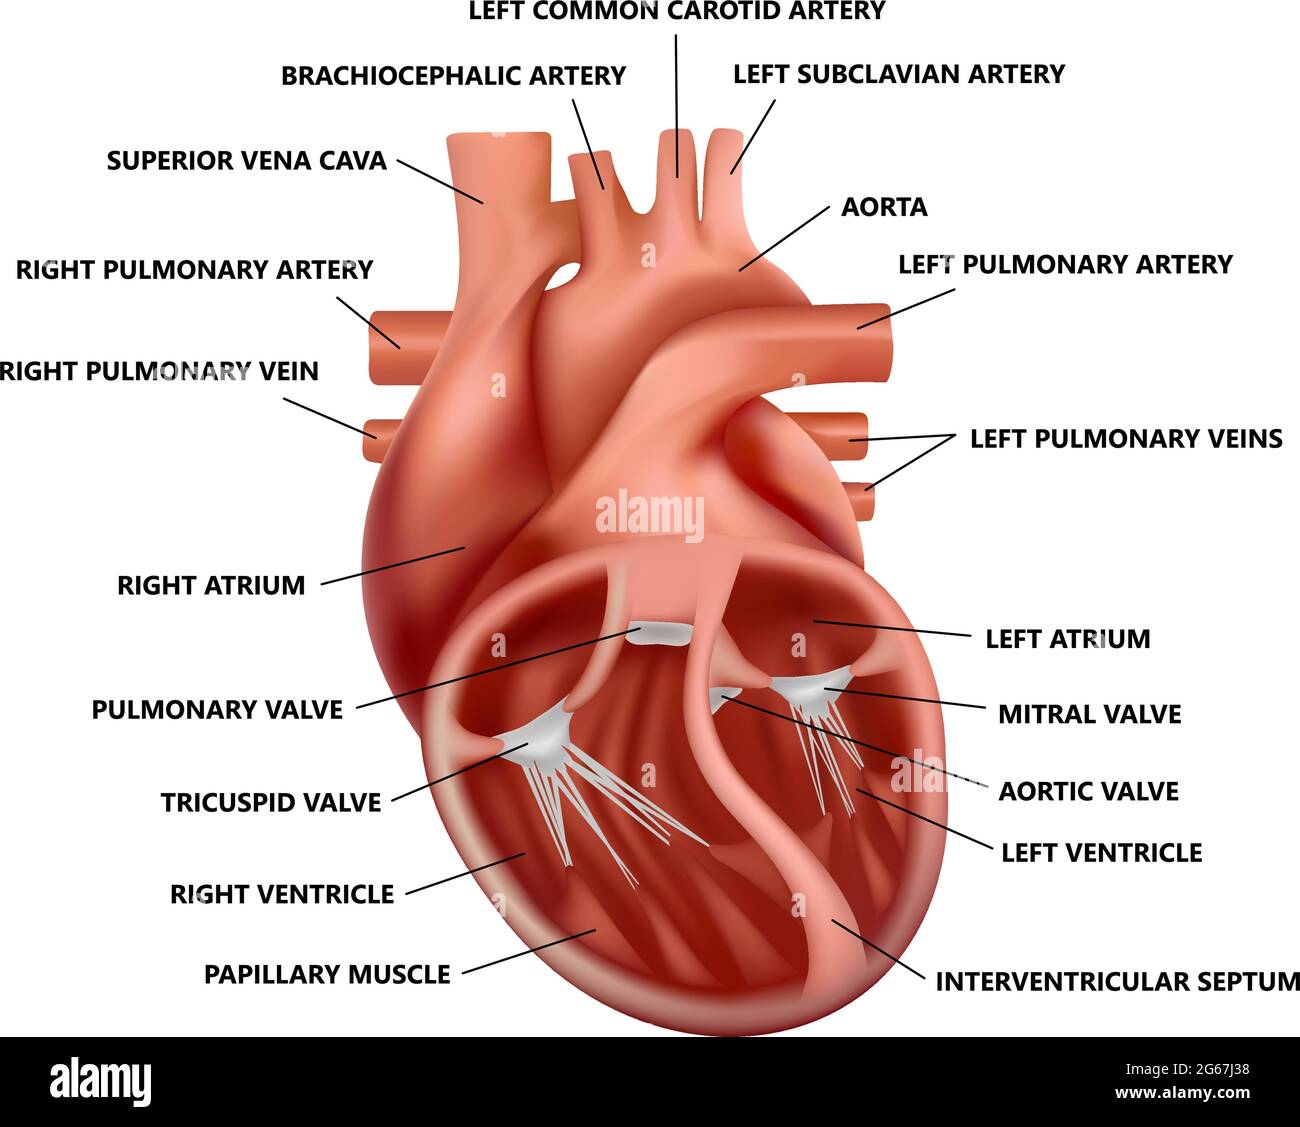

Realistic heart anatomy with descriptions. Diagram of human heart illustration. Stock Vectorhttps://www.alamy.com/image-license-details/?v=1https://www.alamy.com/realistic-heart-anatomy-with-descriptions-diagram-of-human-heart-illustration-image433938261.html

Realistic heart anatomy with descriptions. Diagram of human heart illustration. Stock Vectorhttps://www.alamy.com/image-license-details/?v=1https://www.alamy.com/realistic-heart-anatomy-with-descriptions-diagram-of-human-heart-illustration-image433938261.htmlRF2G5YGK1–Realistic heart anatomy with descriptions. Diagram of human heart illustration.

Anatomy of the human heart. Cross sectional diagram of the heart with main parts labeled. Human heart diagram Vector illustration. Educational diagram Stock Vectorhttps://www.alamy.com/image-license-details/?v=1https://www.alamy.com/anatomy-of-the-human-heart-cross-sectional-diagram-of-the-heart-with-main-parts-labeled-human-heart-diagram-vector-illustration-educational-diagram-image551609872.html

Anatomy of the human heart. Cross sectional diagram of the heart with main parts labeled. Human heart diagram Vector illustration. Educational diagram Stock Vectorhttps://www.alamy.com/image-license-details/?v=1https://www.alamy.com/anatomy-of-the-human-heart-cross-sectional-diagram-of-the-heart-with-main-parts-labeled-human-heart-diagram-vector-illustration-educational-diagram-image551609872.htmlRF2R1C00G–Anatomy of the human heart. Cross sectional diagram of the heart with main parts labeled. Human heart diagram Vector illustration. Educational diagram

Realistic cross-section heart anatomy with descriptions. Diagram of human heart illustration. Stock Vectorhttps://www.alamy.com/image-license-details/?v=1https://www.alamy.com/realistic-cross-section-heart-anatomy-with-descriptions-diagram-of-human-heart-illustration-image434115004.html

Realistic cross-section heart anatomy with descriptions. Diagram of human heart illustration. Stock Vectorhttps://www.alamy.com/image-license-details/?v=1https://www.alamy.com/realistic-cross-section-heart-anatomy-with-descriptions-diagram-of-human-heart-illustration-image434115004.htmlRF2G67J38–Realistic cross-section heart anatomy with descriptions. Diagram of human heart illustration.